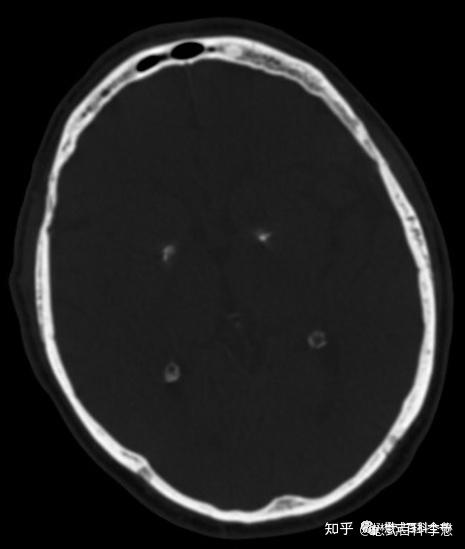

正常脑ct {b}. 苍白球钙化 {c}. 腔隙性脑梗死 {d}. 脑出血 {e}.

11. 可见双侧尾状核,苍白球及皮层下白质对称性高密度影

钙化,转移性钙化病理性钙化右侧尾状核头钙化,呈结节状双侧苍白球钙化